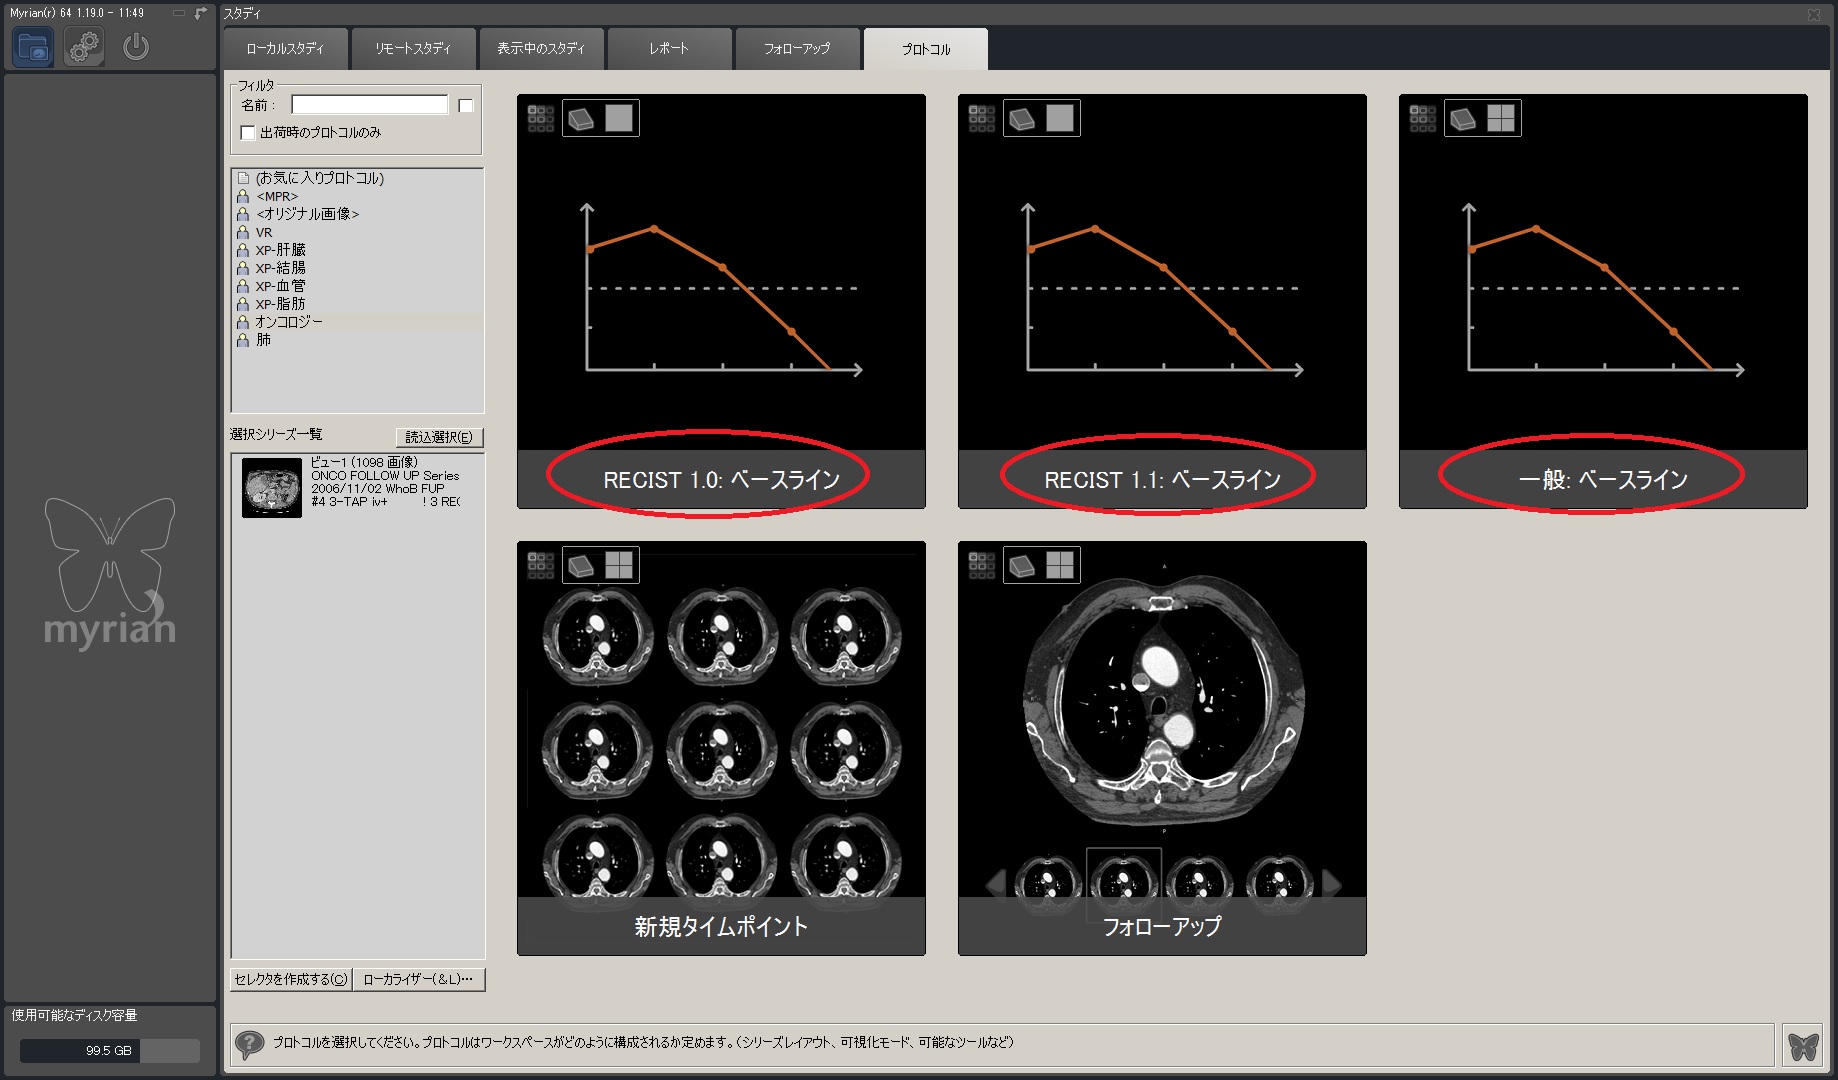

Myrian®XL-Onco 腫瘍の経時的フォローアップ・アプリケーション

効率的なフォローアップのための理想的なソフトウェア

フォローアップに必要なすべてのステップは自動化されています。 ベースライン作成後、次のタイムポイントでは自動的に非剛体レジストレーションが行われ、高速な検査比較が可能です。必要に応じて自動で国際評価基準(RECIST1.0,1.1)に沿った治療レスポンスが計算され、PACSへ転送されます。そし検査レポートも自動作成されます。

| 1.ベースライン作成 |  |

|---|---|

| 2.ターゲット/非ターゲット 各種ROIを計測 、承認 |

|

|

|

| 3.次のタイムポイントでは自動でロードされ、正確に位置合わせたROIを 素早く計測 |